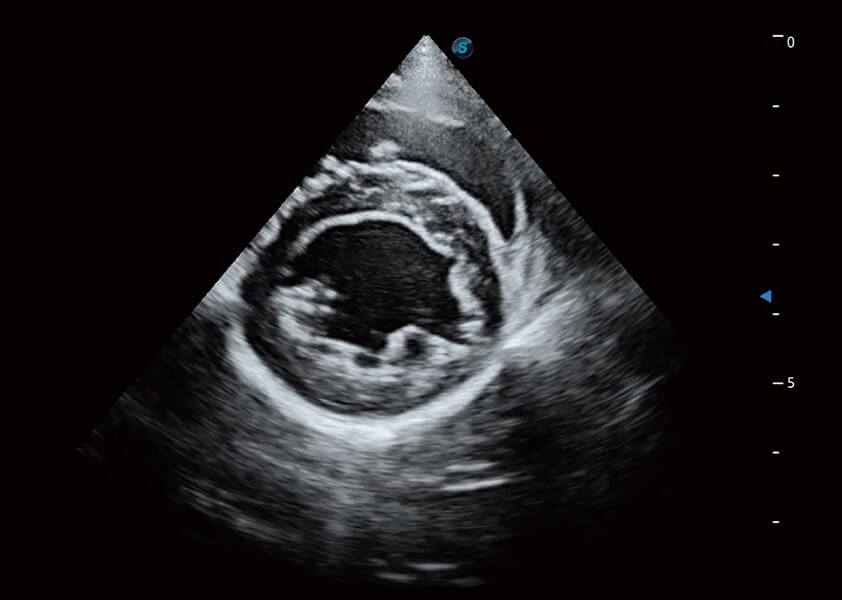

ProPet 60 作为一款高端台式动物超声设备,为动物医生的日常诊断提供了一系列贴合动物临床需求、解决临床实际问题的高级成像功能。凭借全系列高清探头,满足医生对腹部、心脏、生殖、浅表、肌骨等成像的所有需求,切实帮助您提升检查效率,提高诊断信心。

动物是人类最亲密的朋友和最值得信赖的伙伴。乐玩lewin国际也一直致力于探索动物专用的超声影像解决方案。 全新推出的ProPet系列,是乐玩lewin国际在动物超声影像智能化、专业化、精准化的一次跨越式革新。动物不能用言语来表述自己的不适,通过超声影像,ProPet系列搭建了动物医生与不同物种沟通的“桥梁”,为动物医生注入了“治愈之力”。